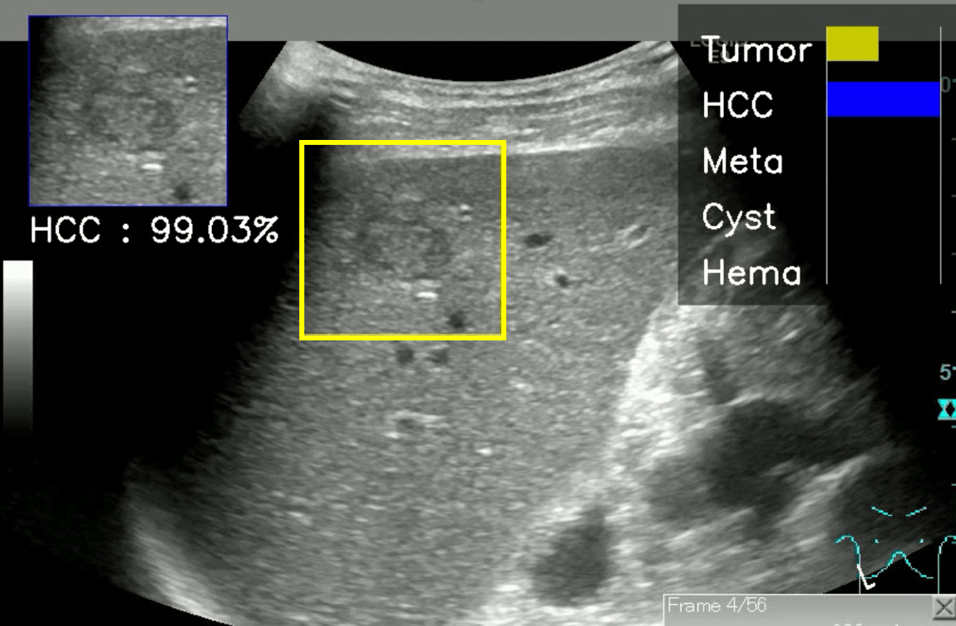

本研究では、テスト用肝腫瘤動画を用いて、AIと熟練医の診断能の比較も行っています。AIの診断にはBモード超音波の動画から5フレームの静止画を選び、3フレーム以上で一番高い推定確率を示す疾患をAIの診断としました。一方、ヒトは静止画のみから診断することは通常極めて困難なため、動画を観察して診断しました。この結果、AIの4疾患鑑別精度は89.1%、悪性腫瘍鑑別精度は90.9%であったのに対して、熟練医5名の4疾患鑑別精度の中央値は67.3%(分布:63.6%~69.1%)、悪性腫瘍鑑別精度の中央値は80.0%(分布:74.5%~83.6%)であり、AIの精度が熟練医の結果を大きく上回りました。また、正しい診断に対するAIの推定確率は、学習データ数が多いほど上昇しており、これはAIが学習を増やすことにより信頼性の高い正解を出力できることを示しています。肝腫瘤のBモード超音波診断において、本AIモデルを活用することにより、非専門医においても熟練医を上回る診断を行うことができると期待されます。